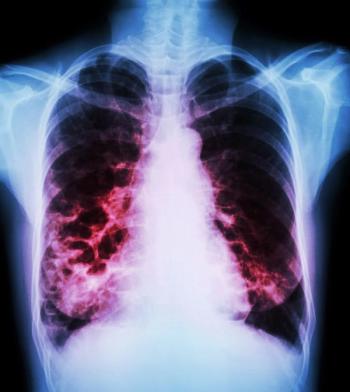

Once again, the USPSTF finds no net benefit to screening asymptomatic persons for COPD. Draft recommendation is available for comment.